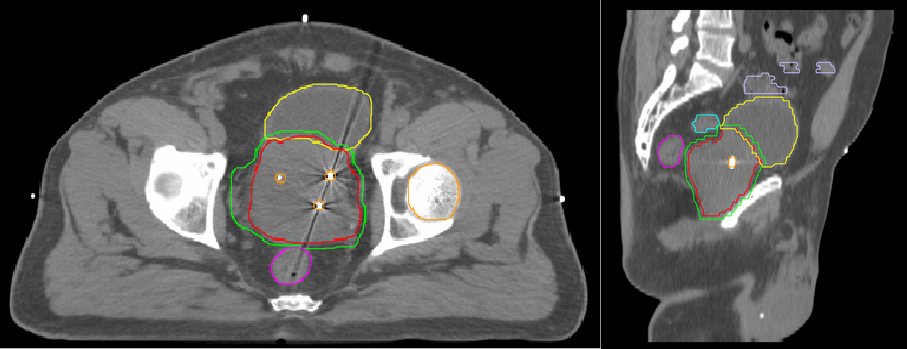

នៅមានជំរើសជាច្រើនទៀត។ ការអភិវឌ្ឍន៍ឲ្យប្រសើរឡើងនៃទម្រង់ការព្យាបាលដោយបាញ់កាំរស្មីពីខាងក្រៅចូលទៅក្នុងរាងកាយសម្រាប់ការព្យាបាលអ្នកជំងឺមហារីកក្រពេញប្រូស្តាតដែលមានហានិភ័យទាបជាង៩០ភាគរយនៃអត្រាព្យាបាល គឺការព្យាបាលដោយប្រើកាំរស្មី(IGRT) ។ ជាដំបូងគឺការដាក់បញ្ចូលជាស្រេចនូវសញ្ញាសំគាល់ទៅក្នុងក្រពេញប្រូស្តាតនូវគ្រាប់មាសតូចៗ3គ្រាប់ បន្ទាប់ពីនោះមកអ្នកជម្ងឺត្រូវបានទទួលនូវបរិមាណកម្រិតកាំរស្មីដោយម៉ាស៊ីនដែលអាចធ្វើការថតស្កែនដោយ CT-scan បាន។ នៅក្នុងរូបភាពដែលបង្ហាញចេញមកនឹងឃើញមាននូវសញ្ញាសំគាល់ទាំង3ចំនុចដែលបានដាក់សម្គាល់ ជួយធ្វើឲ្យលោកគ្រូពេទ្យអាចកំណត់ដុំមហារីកបានកាន់តែច្បាស់។ វិធីនេះជួយកាត់បន្ថយការខូចខាតជាលិកាល្អដែលនៅរុំជុំវិញសាច់មហារីក ថែមទាំងជួយកាត់បន្ថយថេរវេលានៃការព្យាបាលបានច្រើនជាងការព្យាបាលដោយវិធីសាស្ត្រមុនថែមទៀតផង ។